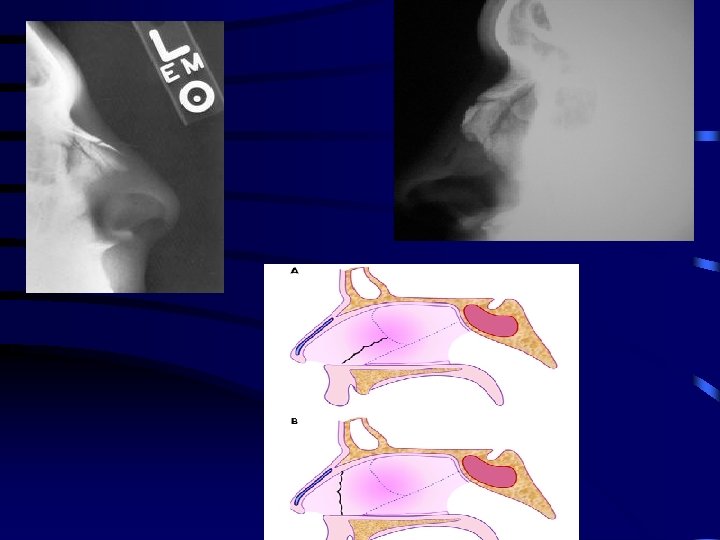

Nasal trauma • Apart from actual fracture of nasal bones, injuries include: - Soft tissue - Septal cartilage fracture - Septal bone fracture - Septal haematoma - CSF leak

Nasal trauma • Injury results from • - lateral - frontal - combined

Clinical features • Signs – External deformity, swelling, lacerations – Tenderness, crepitus – Septal haematoma/ abscess • There is often periorbitaln swelling and there may be periorbital and subconjunctival echymosis

Septal haematoma

Saddle deformity